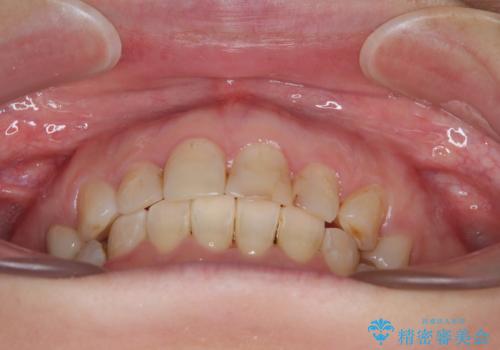

矯正治療後は、気になっていた銀歯を全てセラミックとし、きれいな口元に仕上げることができました。